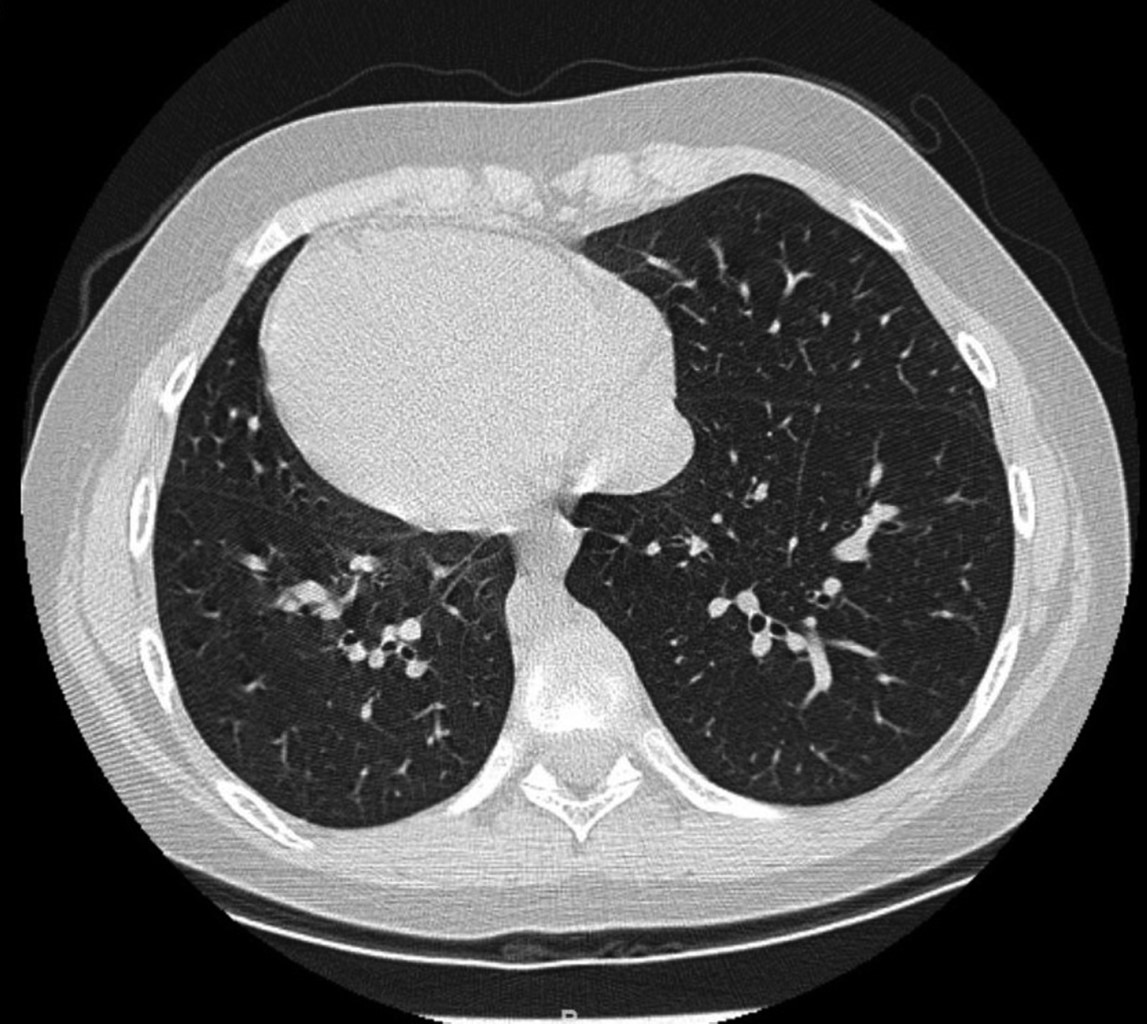

Se realiza analítica sanguínea, proteína C reactiva 94 mg/L, procalcitonina 0.46 ng/mL, Hb 11.7 g/dL, hematocrito 35.6%, leucocitos 20,100, neutrófilos 17,400 (86.4%). Hemocultivo negativo a los cinco días de incubación. Serología negativa para virus respiratorios, incluido micoplasma. Radiografía de tórax (Figura 1) en la que se observa consolidación en lóbulo inferior izquierdo, y opacidades tubulares en esa misma localización, que podrían corresponder con bronquiectasias en paciente con dextrocardia e inversión de vísceras abdominales; este hallazgo junto con las infecciones respiratorias de repetición hicieron sospechar de un síndrome de Kartagener, por lo que se amplía el estudio con tomografía axial computarizada de alta resolución (TACAR) torácica (Figura 2), descartando la existencia de bronquiectasias.

Figura 1